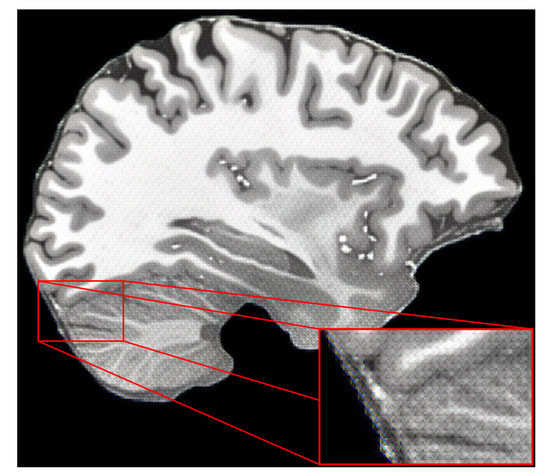

4.3. Results